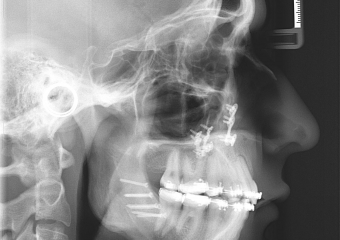

Raio x inicial